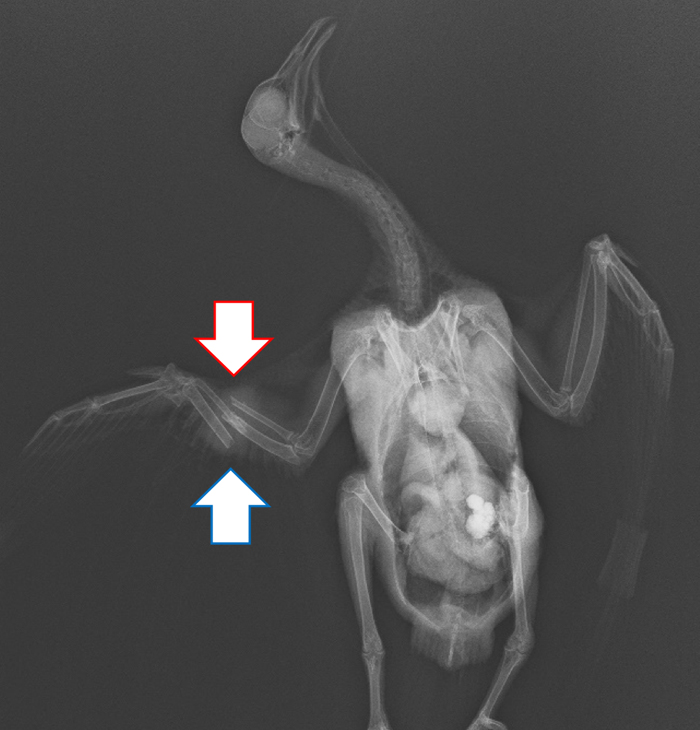

若鳥の搬入時のレントゲン写真。

骨が折れてずれている

(赤矢印:橈骨 青矢印:尺骨) | 若鳥の退院前のレントゲン写真。

骨はしっかりとくっついている

(赤矢印:橈骨 青矢印:尺骨) |